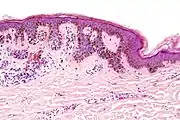

Melanocytic nevi can mainly be classified by depth, being congenital versus acquired, and/or specific dermatoscopy or histopathology patterns:

- Depth

| Depth class | Location of nevus cells | Other characteristics | Image | ICD |

|---|---|---|---|---|

| Junctional nevus | Along the junction of the epidermis and the underlying dermis.[17] | May be colored and slightly raised.[18] | ![]() |

ICD10: D22 ICDO: M8740/0 |

| Compound nevus | Both the epidermis and dermis.[19] | ![]() |

ICD10: D22 (ILDS D22.L14) ICDO: 8760/0 | |

| Intradermal nevus | Within the dermis. | A classic mole or birthmark. It typically appears as an elevated, dome-shaped bump on the surface of the skin.[20] | ![]() |

Small dermal nevus, with nests of nevus cells (arrows)